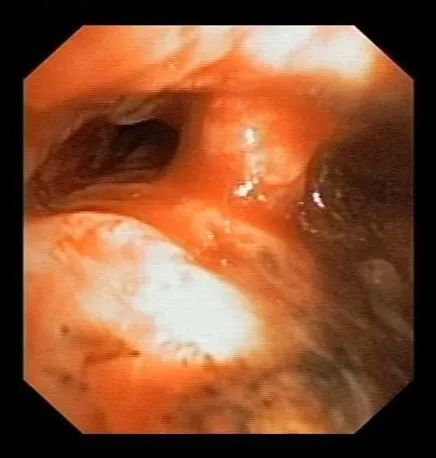

术后复查胸部CT,示气管支气管管壁增厚及管腔狭窄较前减轻

术后复查支气管镜,示气管支气管管腔狭窄较前明显改善,隆突显露